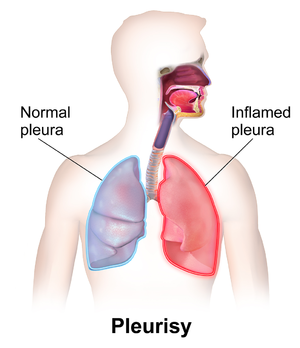

ذاتُ الجَنَب Pleurisy مصطلح عام لالتهاب غشاء الجنب، الذي يبطن داخل الصدر، ويغطي الرئتين. انظر: غشاء الجنب. وجانبا الغشاء رطبان عادة، ويسمحان للرئتين بالتحرك بسهولة على جدار الصدر عندما يتنفس الشخص. وعند التهاب سطْحَي الغشاء، يصبح جافا وخشناً ويحتك بعضه مع بعضه الآخر. وينشط الالتهاب مستقبلات الألم في البطانة الجنبوية داخل الصدر، ويسبب ألمًا حادًا، ويصير أسوأ عند السعال أو التنفس بعمق.